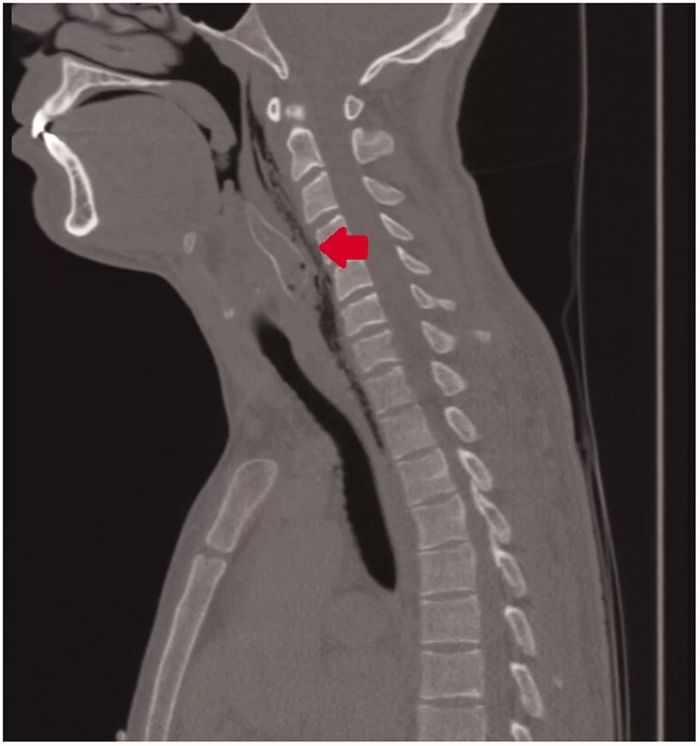

Tidak mengejutkan jika malam itu, pria berusia 28 tahun yang menelan ikan hidup-hidup masuk ruang gawat darurat.

Dokter yang dibuat bingung, mengeluarkan ikan berduri dari tenggorokan pria itu dengan hati-hati.

Tubuh ikan yang memiliki panjang 5 hingga 8 cm dilindungi dengan duri yang terletak pada sirip dada.